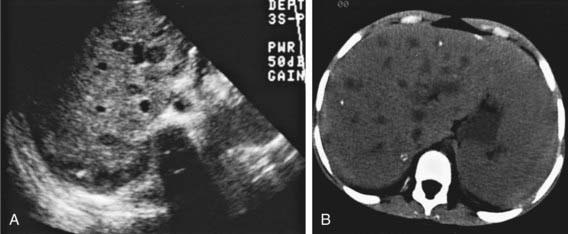

Figure 351-2 Hepatic candidiasis. Transverse sonogram (A) and CT scan (B) of the upper abdomen demonstrate “bull’s-eye” lesions in the right lobe of the liver in an immunocompromised patient. The calcifications seen on the CT scan are presumed to represent sequelae of prior infection. Liver biopsy demonstrated candidiasis.

(From Kuhn JP, Slovis TL, Haller JO: Caffrey’s pediatric diagnostic imaging, vol 2, ed 10, Philadelphia, 2004, Mosby, p 1472.)